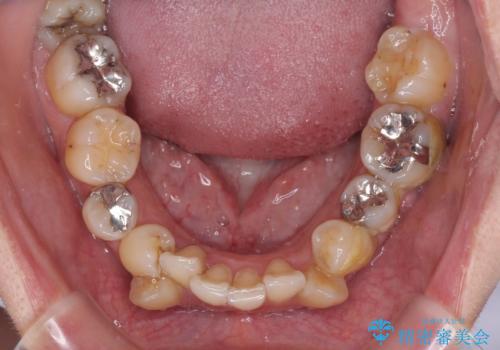

【モニター】上下の八重歯を治したい ワイヤー装置による矯正治療

- 上下前歯のデコボコを気にして来院された患者様です。

デコボコが強いため、非抜歯で矯正をすると出っ歯仕上がりとなるため、上下左右の第一小臼歯4本を抜歯することとしました。